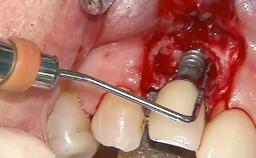

Peri-Implantitis Modified by the Presence of Submucosal Excess Cement: Reconstructive Therapy and a Ten-Year Follow-up

This case outlines the reconstructive therapy by Giovanni Salvi resulting in defect fill and inflammation-free peri-implant soft tissues at 10-year follow up. This case highlights the importance of regular monitoring of implants during supportive therapy.

A 30-year-old female patient was referred to the Department of Periodontology of the University of Bern, Switzerland, by a private dentist. Tooth 45 was congenitally missing and had been replaced with an implant three years prior to the first visit at the Department of Periodontology.